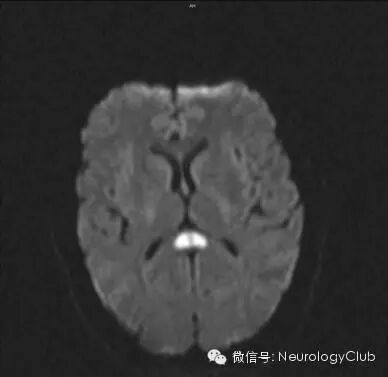

(32岁男性HaNDL患者,DWI可见胼胝体压部弥散受限,5周后复查病灶完全消失)

常规头颅CT和MRl多数正常,也有出现可逆性胼胝体压部病变的报道。MRA和DSA检查一般也无颅内血管病变的证据。CT或MR灌注成像可提示局灶低灌注,SPECT上可见局灶放射性核素摄取降低,其部位多与临床症状相符。脑电图提示的局灶慢波区域亦与局灶性神经功能缺损定位相一致。